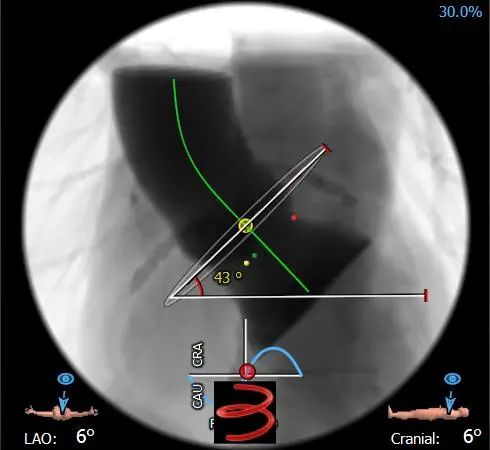

该患者全心扩大,瓣环与水平成角常规,瓣环较大(周长约87mm),流出道周长月94mm且流出道长度短,形态程喇叭口状。双侧冠脉开口较高,窦宽较宽,窦管结合部直径及高度良好。整体冠脉闭塞风险较低,瓣膜移位风险较高。

瓣膜释放前定位